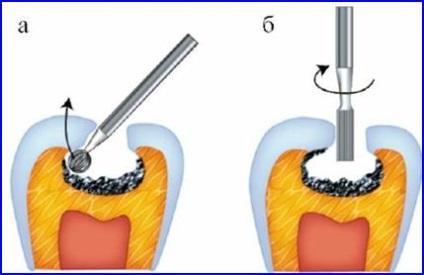

- Fissurotomiya. Ezt a módszert alkalmazzák a legvégső, amikor arra szükség van, hogy felfedje a repedések a teljes figyelmet a kép a vereség. Az eljárás alkalmazását foglalja magában olyan eszközöket karbid bojtorján, amely ismerteti a teljes szuvas régió nem több, mint 0,6-1,1 mm, amely egyenlő a vastagsága a zománc réteg a fog.

Feldolgozása az üreg a fogat

Tömítő végzi fúrás megbetegedett szövetet, majd azt megtöltjük kompozitok megkeményedik a fény hatására vagy üveg - ionomer cementek.